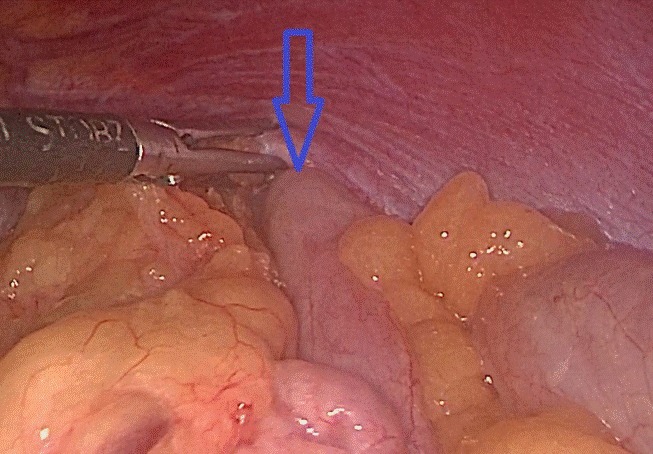

Tại đây, bệnh nhân H. đã được chỉ định mổ nội soi để sửa tổn thương và phục hồi cơ hoành. Khi đưa máy soi vào ổ bụng, phẫu thuật viên nhận thấy gần toàn bộ đại tràng ngang, lách, dạ dày và mạc nối lớn đã chui qua cơ hoành lên khoang màng phổi bên trái. Sau khi đưa các tạng trên trở lại ổ bụng, tổn thương cơ hoành bên trái lộ rõ là một lỗ khuyết rộng khoảng 6x8 cm.

Đây chính là nguyên nhân gây ra thoát vị, kết hợp với tiền sử có chấn thương, chẩn đoán trong mổ là thoát vị hoành trái do vỡ cơ hoành. Cơ hoành vỡ đã được các phẫu thuật viên khâu phục hồi kín, ca mổ diễn ra trong 1 giờ 30 phút. Sau mổ, bệnh nhân ổn định, hết đau ngực, khó thở, chụp phim X.quang kiểm tra thấy phổi nở tốt, không còn hình ảnh thoát vị. Bệnh nhân H. được ra viện sau 6 ngày với sẹo mổ rất nhỏ của phẫu thuật nội soi.